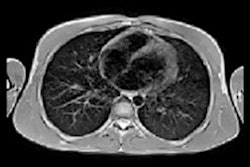

In a standard radiological workflow, patients are transported from the ward to radiology for imaging, which can introduce considerable risks. Low-field MRI systems can be made portable and thus reverse the workflow by bringing the scanner to the patient, a concept realised with portable ultrasound, x-ray, and CT scanners. One direct application of low-field MRI is stroke imaging where a portable system taken to the patient can reduce the time to imaging, which is crucial for deciding on appropriate treatment.1